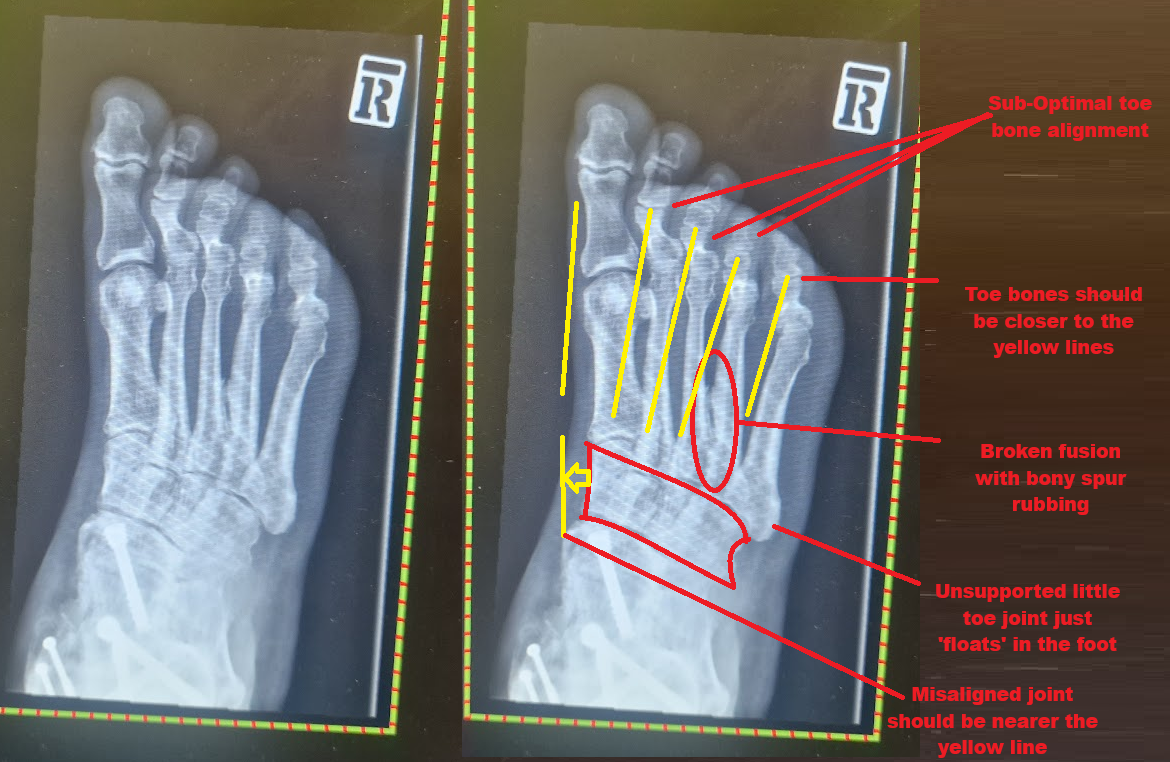

The problem through the foot is from a separate injury where I kicked a tree stump with enough speed to bend the pedal arm up under the frame. This also meant my toes were pushed backwards and snapped most of the metatarsals. Now my metatarsals in my foot, instead of pointing straight backwards, point about 30° to the right. The metatarsals then sort of fused together. But in a third unrelated crash, I managed to break some of this fusion. This means the broken bits of the fusion rub against each other, which is where the pain comes from when trying to pedal or walk. I spoke to the doctor, but he says my foot's so smashed up they weren't able to do anything useful to improve it, so I guess I just live with it.